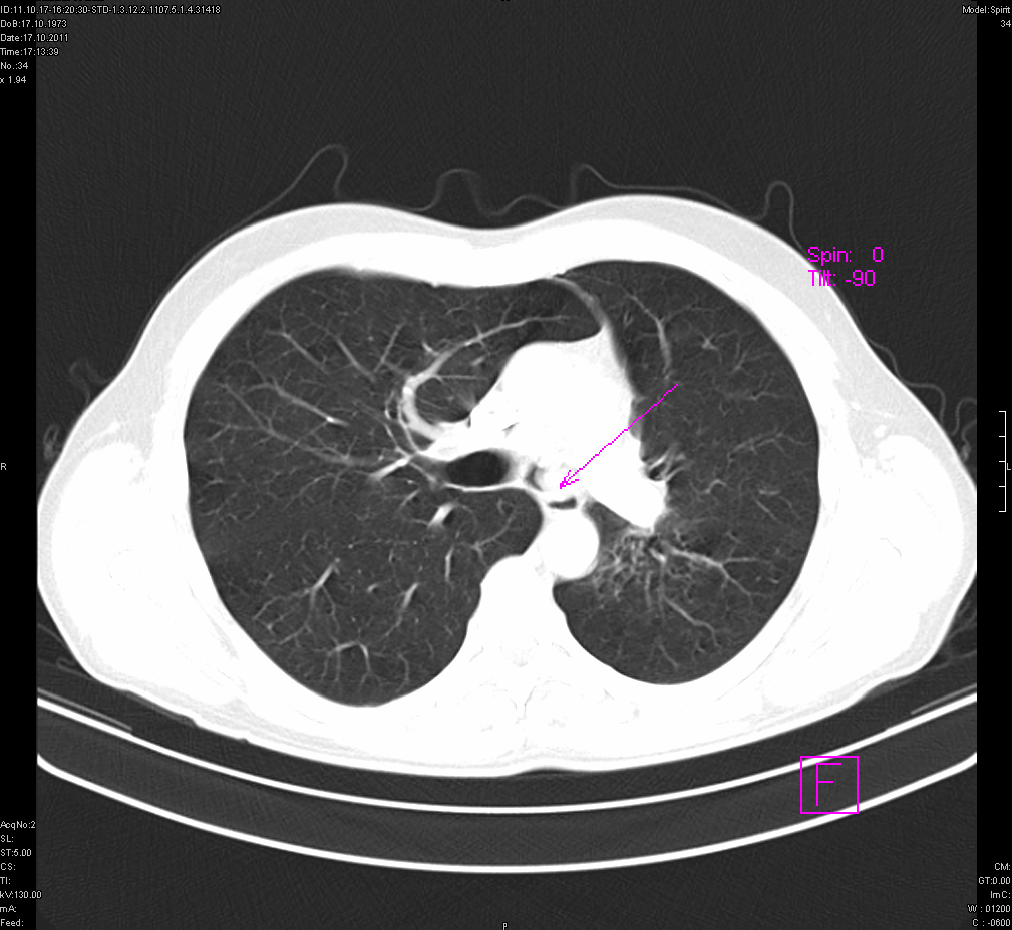

- გულმკერდის კტ (Axial) რეზექციამდე 5 თვით ადრე.

გულმკერდის კტ რეზექციამდე (Axial)